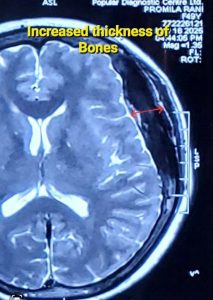

খুলিতে প্যাগেট’স ডিজিজ (Paget’s Disease of Skull)

প্যাগেট’স ডিজিজ শরীরের যেকোনো হাড়কে প্রভাবিত করতে পারে, তবে প্রায়শই এটি পেলভিস (শ্রোণী), মেরুদণ্ড, পা এবং মাথার খুলিকে প্রভাবিত করে। যখন এটি মাথার খুলিকে প্রভাবিত করে, তখন কিছু নির্দিষ্ট সমস্যা দেখা যায়।

মাথার খুলিতে প্যাগেট’স ডিজিজের প্রধান লক্ষণগুলো হল:

* মাথার খুলির আকার বৃদ্ধি (Enlargement of Skull): মাথার খুলির হাড় বড় বা বিকৃত হতে পারে, যার ফলে মাথা বড় মনে হতে পারে। কখনো কখনো টুপি বা হেলমেট পরতে অসুবিধা হতে পারে।

* এক্স-রে (X-rays), MRI এবং CT Scan: আক্রান্ত হাড়ের অস্বাভাবিক গঠন, যেমন ঘন হওয়া বা বিকৃতি ধরা পড়ে।